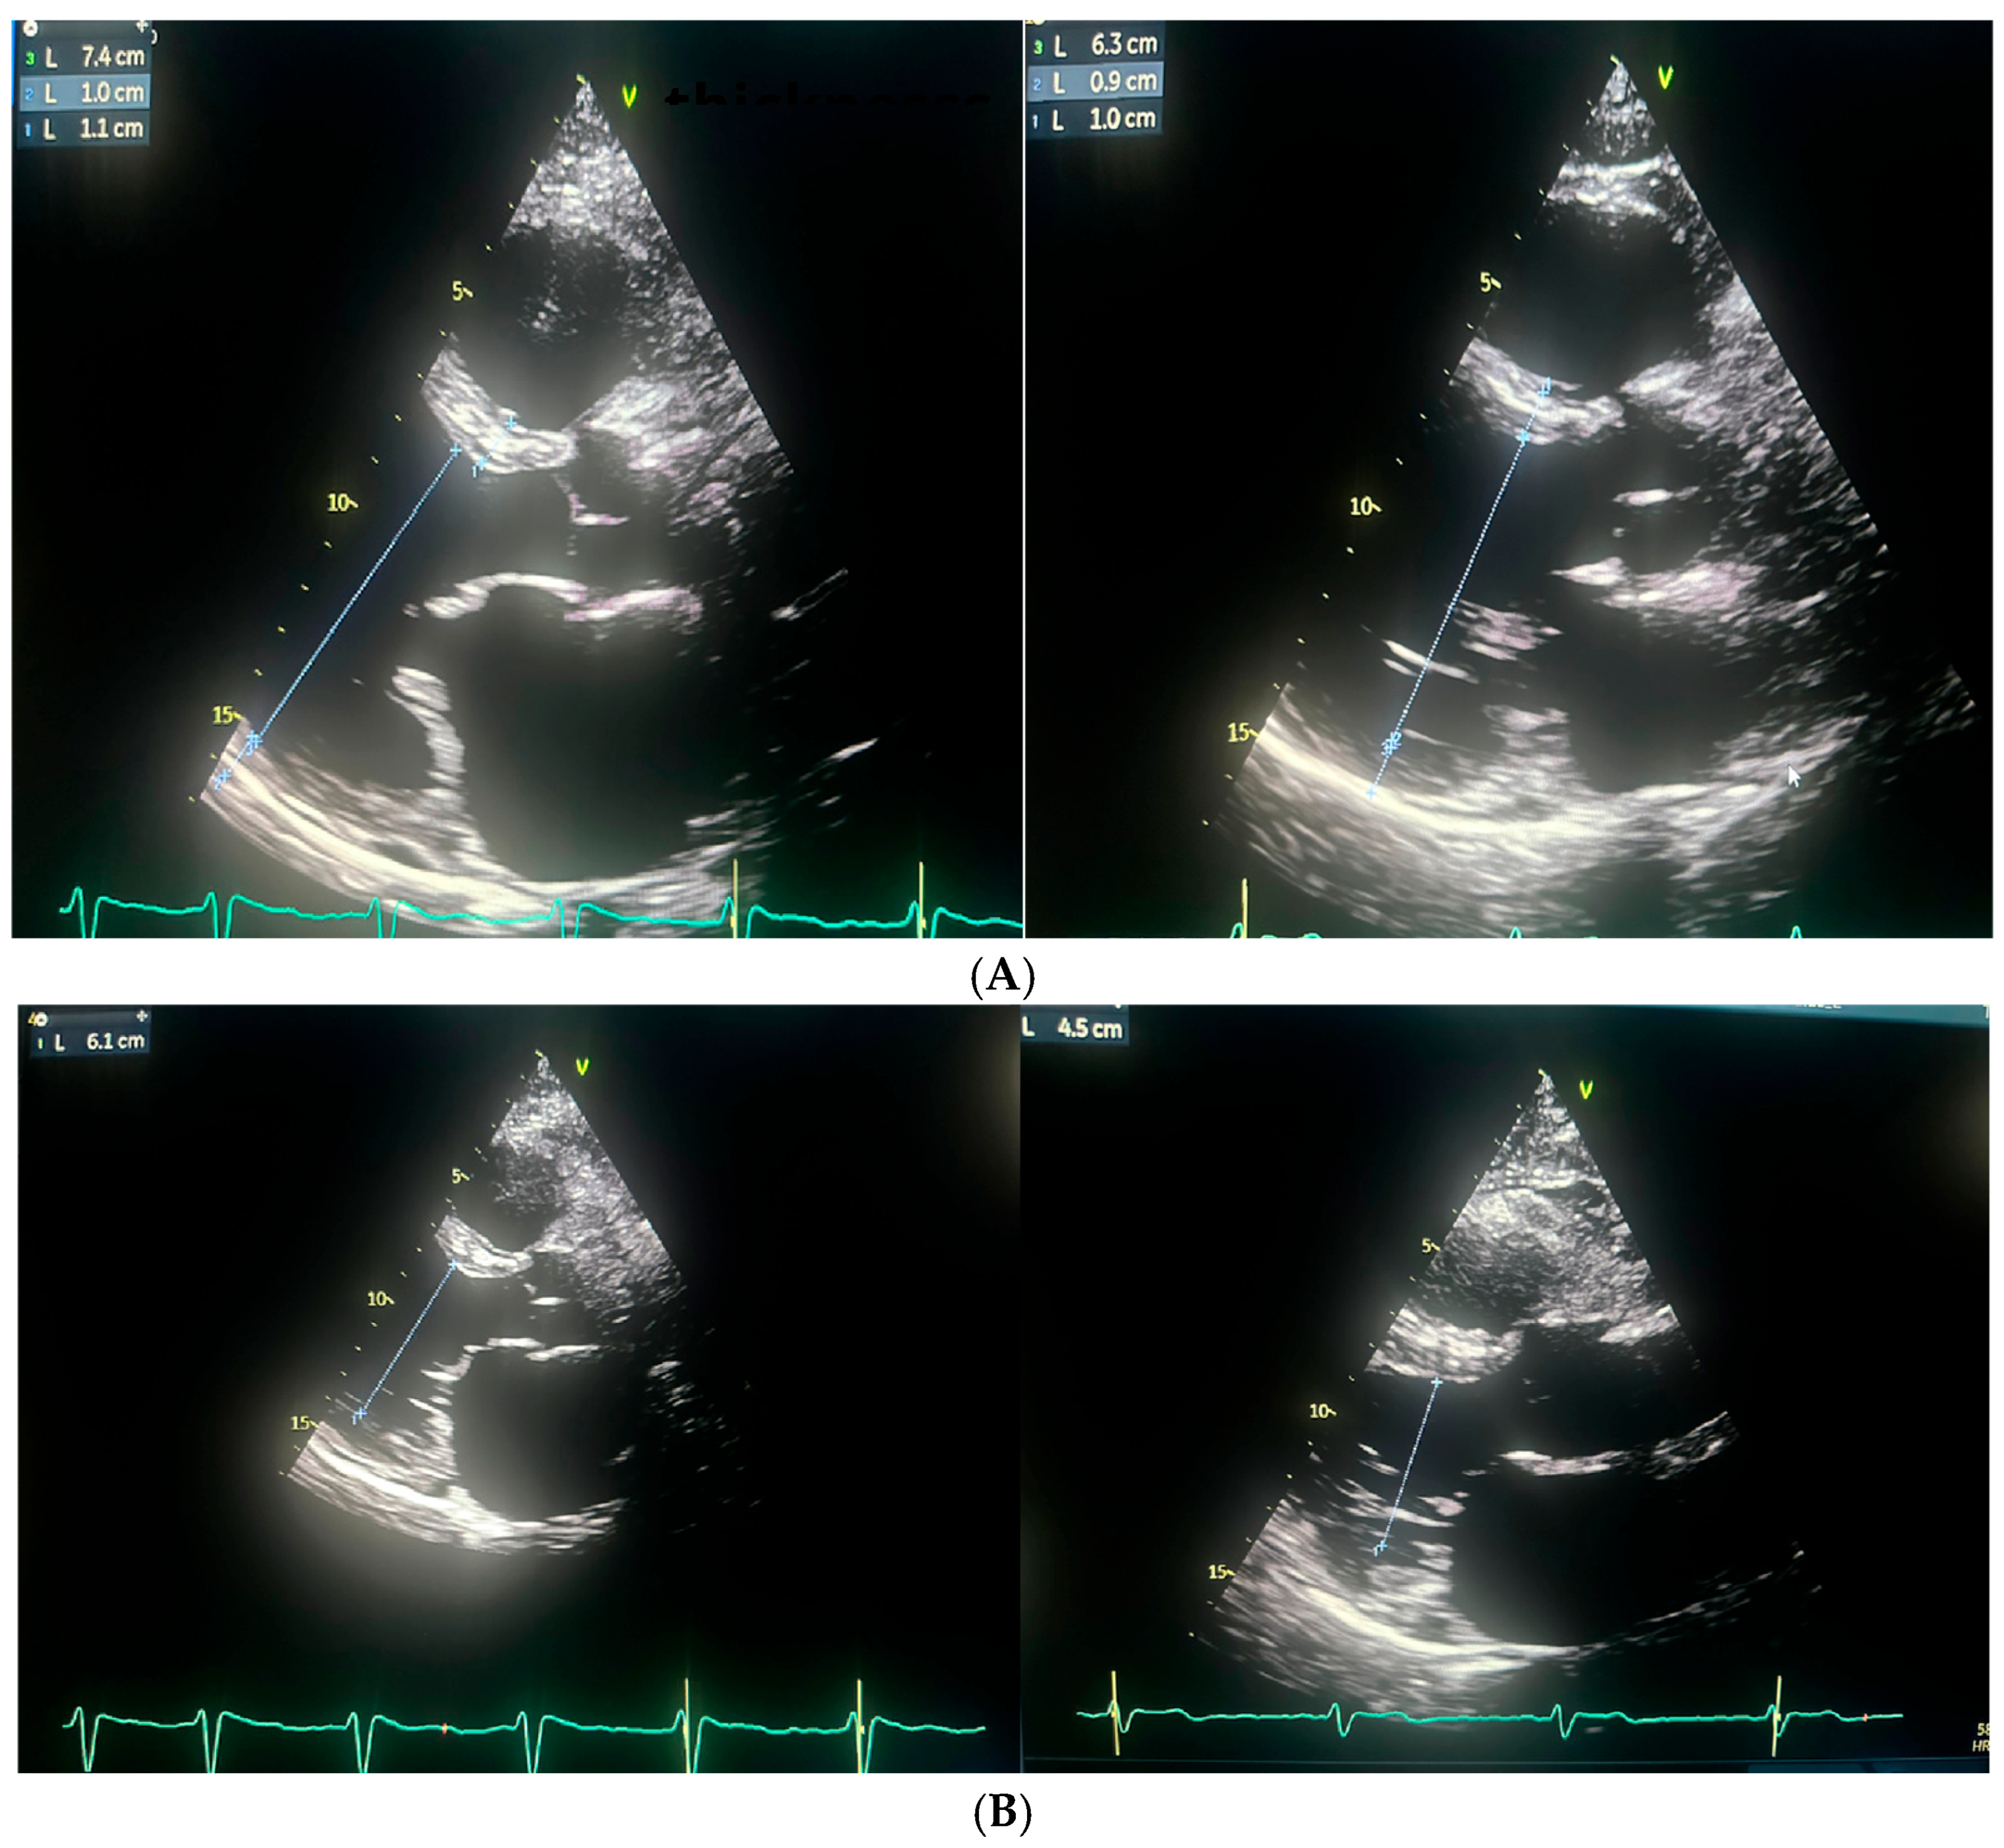

| Echocardiographic Parameters | First Admission | Ablation | Follow-Up |

|---|---|---|---|

| LVEF (%) | 25 | 27 | 54 |

| LVEDD (mm) | 61 | 74 | 63 |

| LVESD (mm) | 55 | 61 | 45 |

| LA (mm) | 48 | 54 | 45 |

| LAA (cm2) | - | 36.2 | 23 |

| LAVI (ml/m2) | - | 60.25 | 36.6 |

| RAA (cm2) | - | 22.8 | 21.5 |

| TAPSE (mm) | - | 18 | 23 |

| PALS (%) | - | 5 | 20 |

| RVSP (mmHg) | 37 | 40 | - |